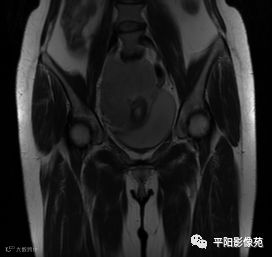

MRI表现

T2冠状位

(宫腔内见金属节育环伪影)宫颈区见不规则形等T1稍长T2信号软组织肿块,DWI序列呈明显高信号,大小约为3.87cmX2.64cm,双侧宫颈基质低信号环连续性中断,病灶向子宫右后上方生长,周围脂肪间隙模糊,增强扫描明显强化,强化程度低于子宫及宫颈实质;子宫后方、子宫直肠间隙见不规则形长T1长T2信号软组织肿块,DWI序列呈高信号,大小约10.12cmX4.82cmX10.29cm,病灶呈分叶状,向下方生长与宫颈分界不清,与直肠分界尚清,增强扫描明显不均匀强化。